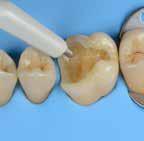

Why deep margin elevation?

Deep margin elevation will make the impression easier by moving the proximal margin of the restoration supra-gingivally, which is especially important for intra-oral scanning. It helps in avoiding periodontal surgical procedures. It makes isolation of the prepared tooth and luting of the final restoration easier.

Tips and Tricks

• Isolation with rubber dam is highly recommended.

• For a better emergence profile, use Teflon tape in the space between the matrix and the adjacent tooth instead of a wedge. Do not use the same matrix as you use for creating a contact point in direct restorations.

• Selective etching of the enamel is recommended.

• Use XBW shade of G-aenial® Universal Injectable for easy differentiation between the tooth, composite material and the restoration.

• The height of the new margin should be slightly above the gingival margin (1mm).

any overhangs. Expose the enamel

1. Clean the tooth surfaces, rinse thoroughly and dry.

2. Apply a matrix adapted to the technique. Gingival margin of the preparation should be well sealed.

3. Etch the enamel.

5. Dry and light-cure.

6. Apply G-ænial Universal Injectable to the gingival margin of the proximal box.

7. Light cure

8. Remove the matrix and check for

covered with adhesive on the rest of the tooth with a fine grit diamond bur.

4. Apply a bonding agent (G-Premio BOND or G2-BOND Universal).